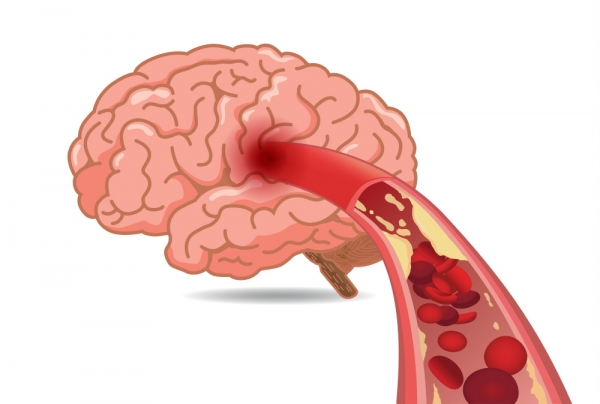

뇌경색 초기증상에 대하므로 살펴볼게요니다. 뇌에도 혈관이 있어서 피가 흐르고 있어요. 뇌에 있는 혈관이 막혀서 뇌의 일부가 손상되는 것을 뇌경색이라고 말해요. 뇌혈관이 막혀 뇌가 손상되면 장애가 발생할수 도 있으므로 뇌 연관 질환은 각별한 주의가 필요해요.

뇌에 제공되는 혈액량이 줄어들게면 뇌가 수습해야 되는 역할들을 제대로 실행해 낼 수 없게 돼요. 뇌혈류가 연속적으로 감소되면 뇌조직에 괴사가 시작되고 괴사된 뇌조직이 회복 불가능한 상태가 되면 뇌경색이라고 진단을합니다. 그러므로 뇌경색 초기증상을 알아두고 방지해억제해하시는게 중요해요.

뇌경색의 주된 이유가 되는 것은 혈전이지요. 혈전이란 혈관 속에 피가 굳어진 덩어리를 얘기하는데 이것이 혈관을 막는 것이 뇌경색에 큰 영향을 줄 수 있습니다. 평균적으로 많이 발생하는 연령대는 5~60대이지요. 뇌경색은 양쪽 뇌에 모두 나타나는는 것이 아니라 주로 한쪽 뇌에만 발생하지만, 주로 한쪽 팔다리가 마비되었다거나 얼굴 근육이 굳어버리기도 해요. 그렇기에 뇌경색 초기증상이 발생한다면 민첩하게 대응를 해야 하겠습니다.

또 뇌경색의 까닭은 혈관의 협착을 유발시키는 동맥경화증이고요. 동양에서는 뇌내동맥경화증이, 서양에서는 경동맥동맥경화증이 많이 나타나고다. 그리고 흡연, 고지혈증, 당뇨병, 고혈압, 건강에 옳지 않은 식습관, 스트레스 등도 뇌경색을 발생시키는 위험요인입니다.모든 질병에 단일 이유가 되는 것이 없듯이 뇌경색도 단일 이유가 되는 것이 아닐 수 있고요.